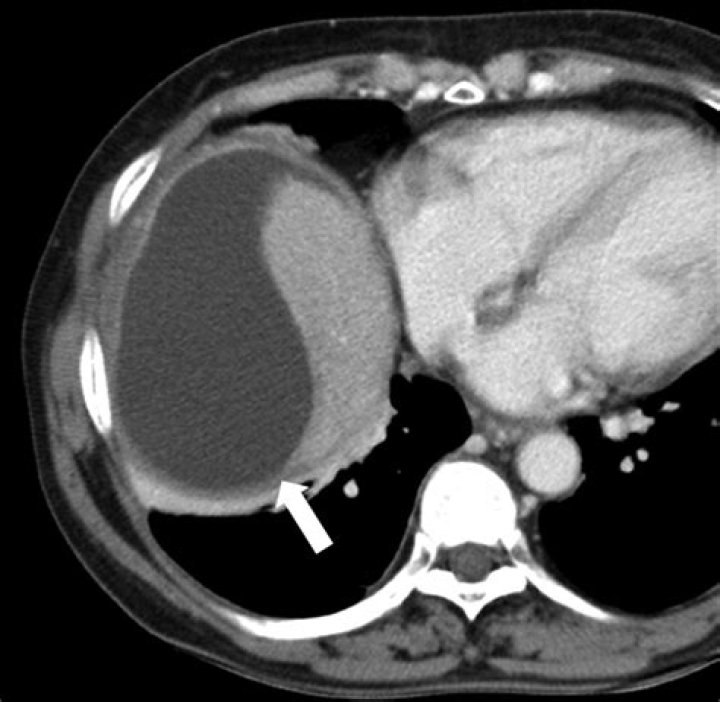

Biloma is collection of bile within the abdominal cavity. It happens when there is a bile leak, for example after surgery for removing the gallbladder (laparoscopic cholecystectomy), with an incidence of 0.3–2%. Other causes are biliary surgery, liver biopsy, abdominal trauma, and, rarely, spontaneous perforation.

A biloma is a rare abnormal accumulation of intrahepatic or extrahepatic bile caused by traumatic or spontaneous rupture of the biliary tree1, 2). It is most commonly caused by surgery, percutaneous transhepatic cholangiography (PTC), percutaneous transhepatic biliary drainage (PTBD), and abdominal trauma11, 12).

Abstract. The term biloma describes an encapsulated collection of bile within the abdomen, usually secondary to bile duct disruption. The commonest causes reported in the literature are iatrogenic (secondary to hepatobiliary surgery), trauma or complications due to choledocholithiasis.